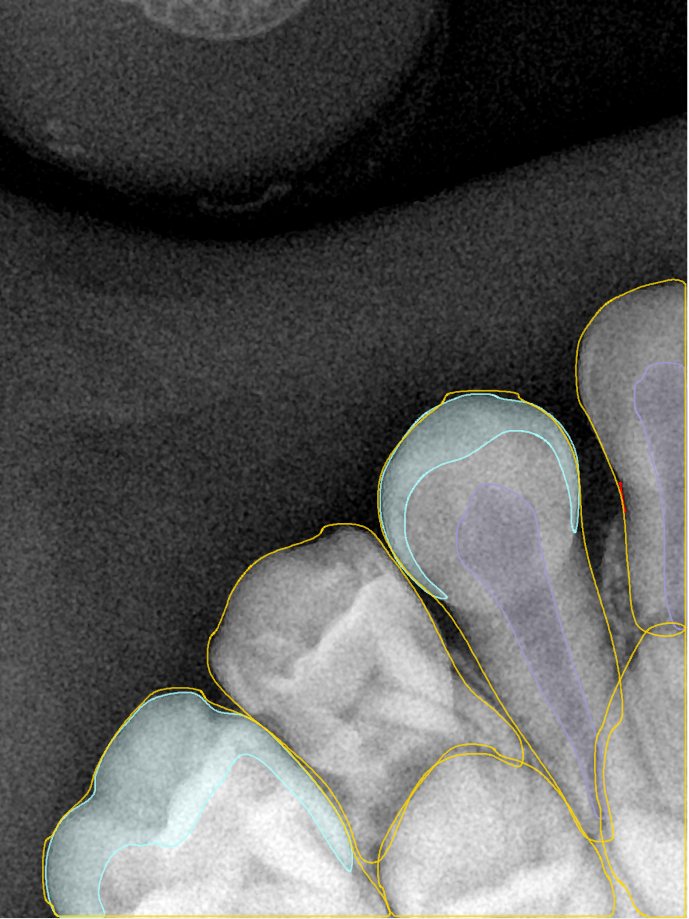

CR/DR 牙齿分割阶段记录

当前进展

- 完成了 CR/DR 牙齿相关分割训练

- 当前结果已经达到阶段预期,但仍有细节问题需要继续处理

相关测试

遇到的问题

- 训练过程中出现过 mask 下移问题

- 部分结果会出现 box 填充异常

- mask 边缘仍然有比较明显的锯齿感

参考

第二版算法问题测试